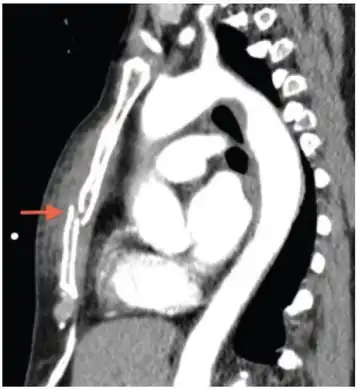

X-rays of the chest are taken in people with chest trauma and symptoms of sternal fractures, and these may be followed by CT scanning.[12] Since X-rays taken from the front may miss the injury, they are taken from the side as well.[13]